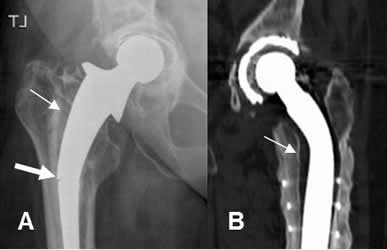

Fig 114. Aflojamiento.

A: Rx AP. Aflojamiento de la prótesis, con un espacio mayor de 2 mm. Adicionalmente hay fractura en el tercio medio del vástago. (Flecha gruesa).

B: TAC reconstrucción coronal. Aflojamiento de la prótesis.